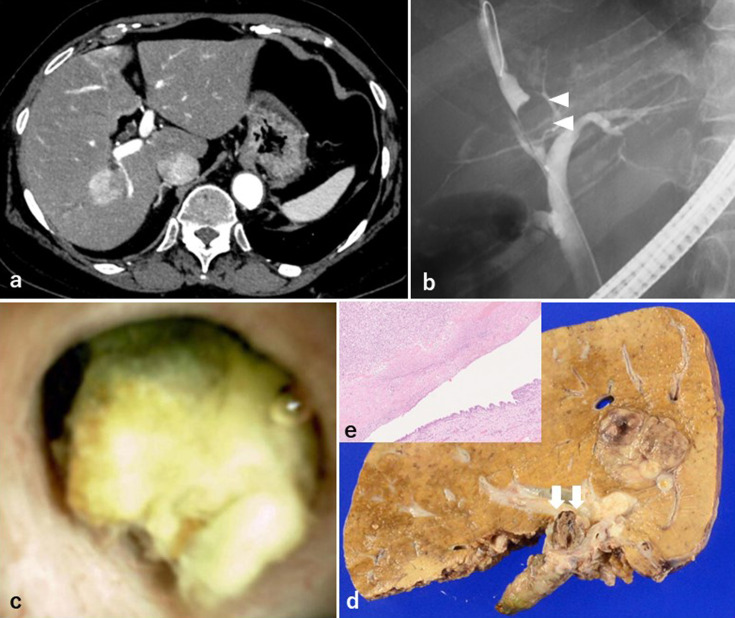

Objective: Bile duct tumor thrombosis in hepatocellular carcinoma (HCC) is a relatively rare event with a poor prognosis. Furthermore, bile duct tumor thrombus in HCC may be misdiagnosed when only imaging modalities are used. The efficiency of peroral cholangioscopy (POCS) in evaluating bile duct lesions has been reported. Patients: We present three cases of HCC with bile duct strictures in which POCS was performed as a preoperative evaluation. Results: In these three cases, diagnosing whether the lesion was a bile duct tumor thrombus on CT and endoscopic retrograde cholangiopancreatography was difficult. We performed POCS in three cases and were able to diagnose the presence of bile duct tumor thrombus of HCC, including differentiation from extrinsic compression of the bile duct. Conclusion: POCS for HCC with bile duct features is useful for the preoperative diagnosis of bile duct tumor thrombus, especially in cases where the surgical procedure depends on the presence of bile duct tumor thrombus.

Abstract Image